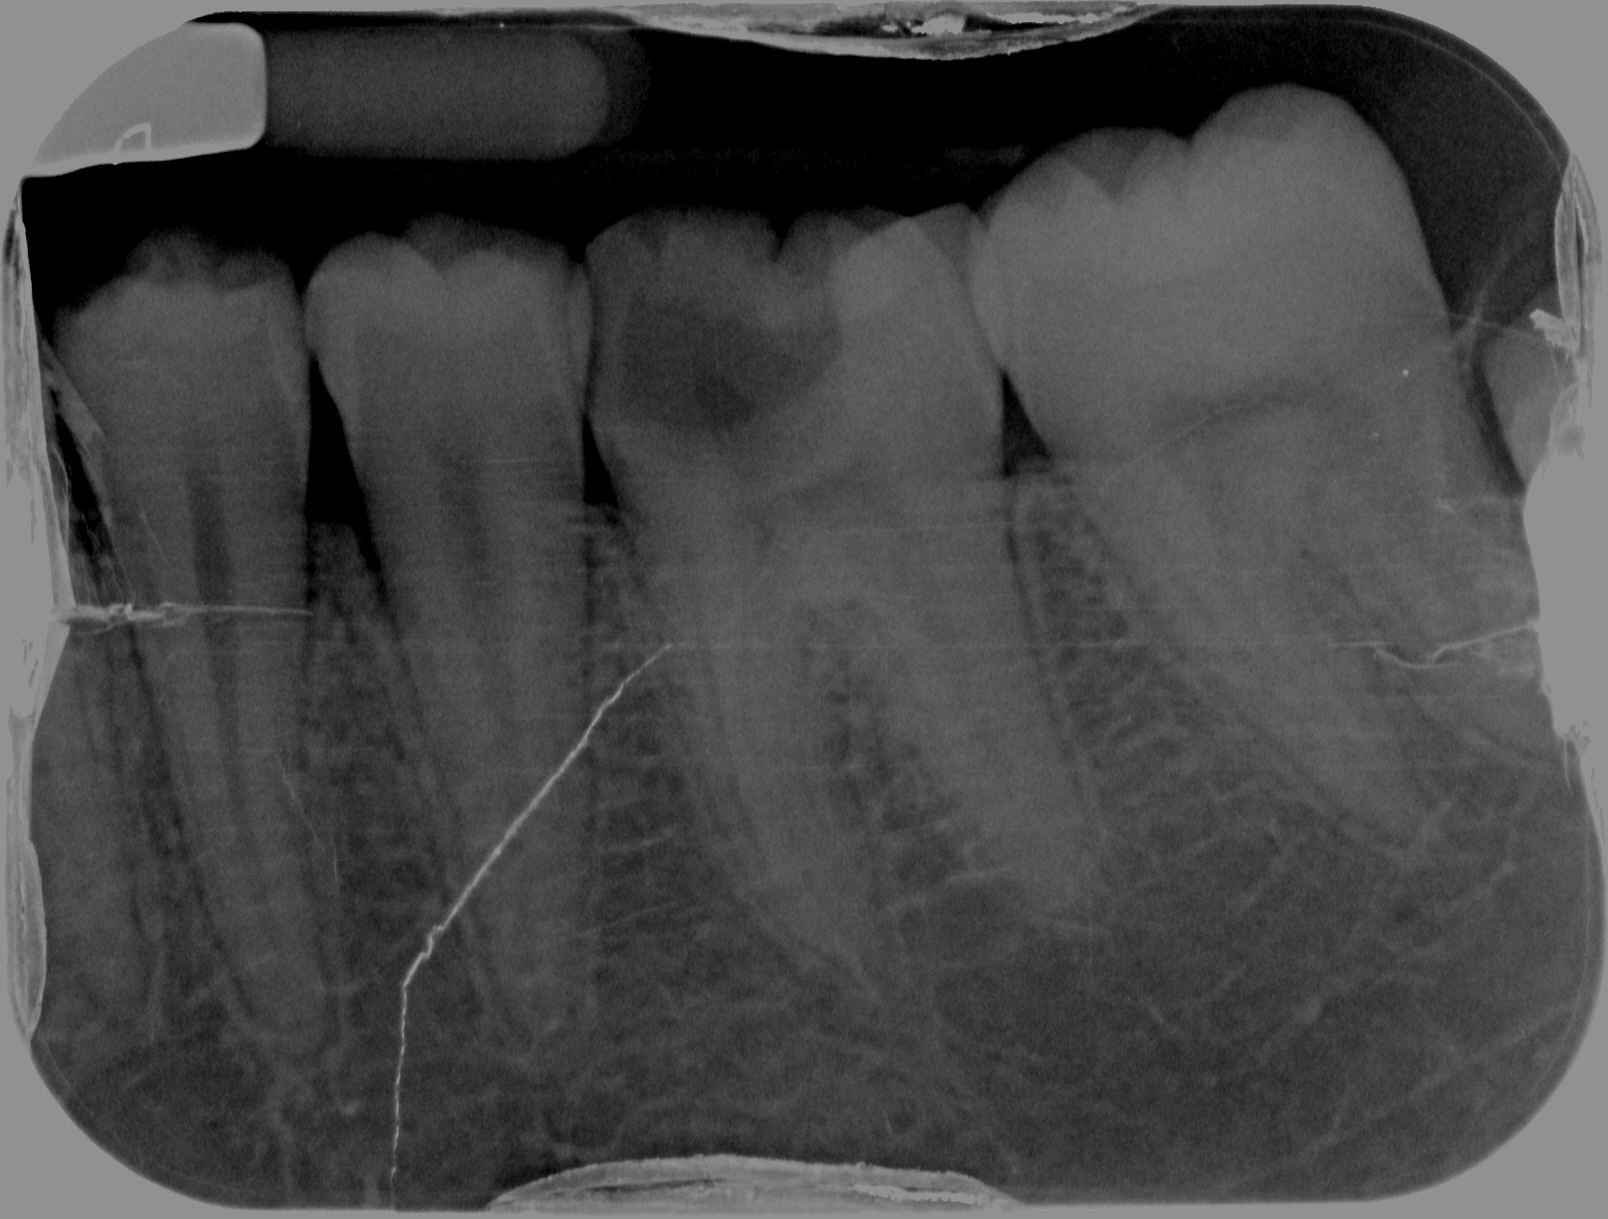

36 NTTP, Cold +ve, vital. 37 O caries

Initial